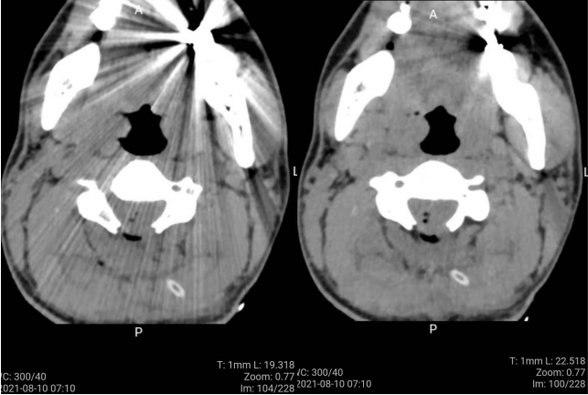

术前经脊髓组陈大刚副主任医师及科室内医师细致分析及讨论,详尽制定了经颈后正中入路颈髓肿瘤切除手术方案及风险预案。于8月9日在手术室、麻醉科及病理室配合下顺利实施手术并镜下全切肿瘤。术中冰冻病理回报为星形细胞瘤2级。术后患者意识恢复,顺利拔除气管插管,患者无呼吸抑制、无肢体瘫痪、无运动感觉障碍、无二便障碍等不良反应,目前患者生命体征平稳恢复中,已经离床活动。

术后第一日CT复查